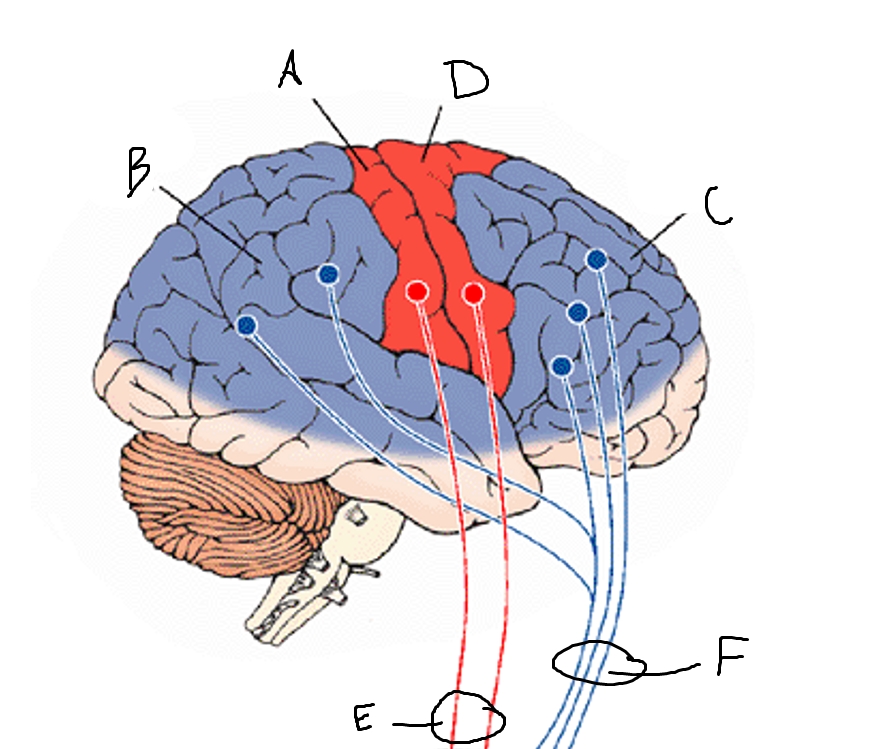

basal ganglia

A

somatosensory cortex

B

parietal association cortex

C

frontal and prefrontal cortices

D

primary motor cortex

E (where are the projections?)

putamen

F (where are the projections?)

caudate